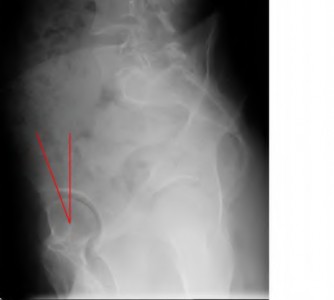

A 72-year-old female presents with progressive left thigh and knee pain for the last year. 5 years ago she sustained a femoral neck fracture treated with the implant seen in Figures A-C (current radiographs). The thigh pain is worse with weight-bearing. C-reactive

protein and erythrocyte sedimentation levels are within defined limits. Which of the following is the most likely cause of her pain?